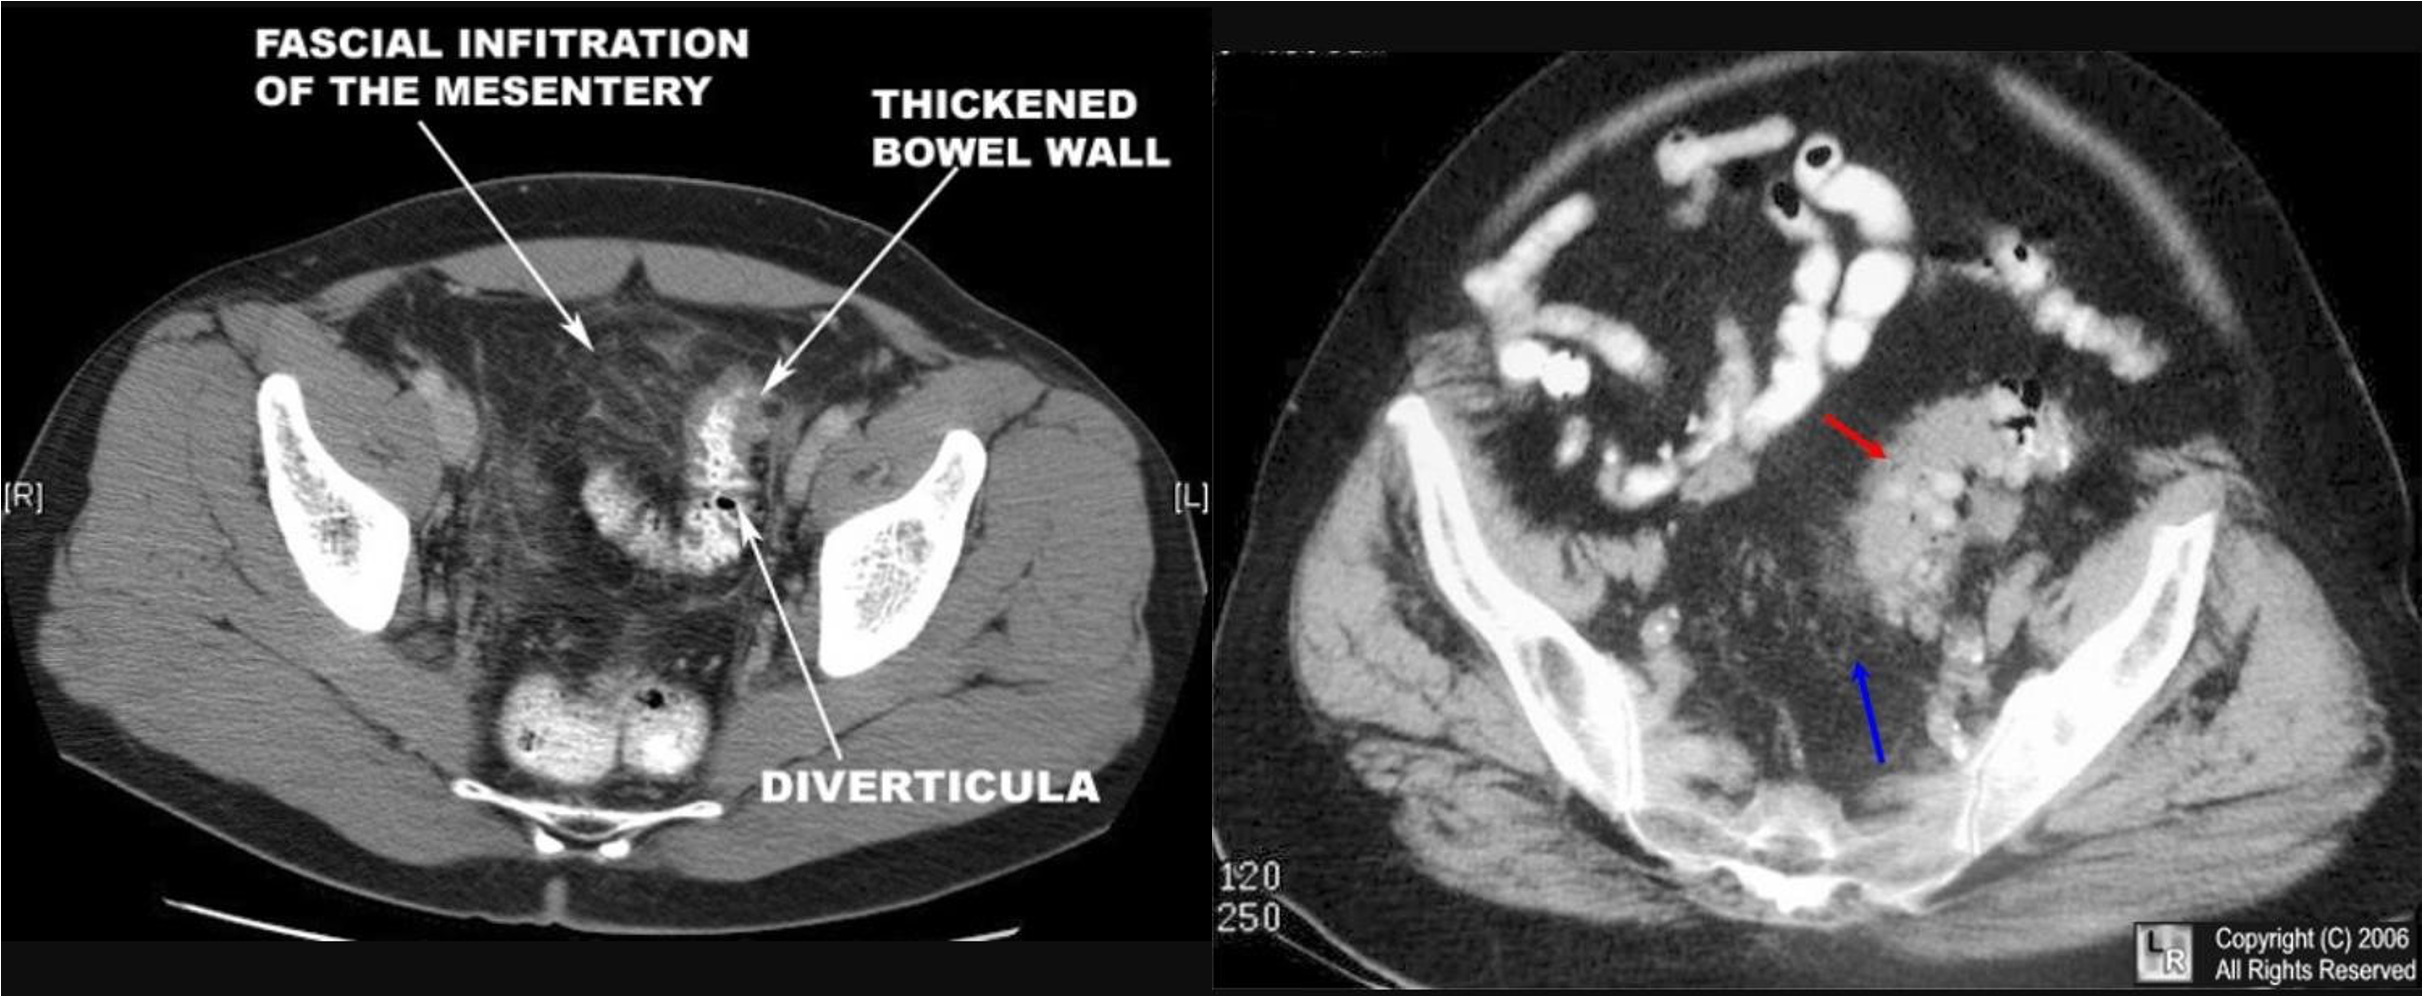

Modality: Gastrography swallow / Barium Enema Findings: apple core / out pouching lesions Differentials: colon cancer / diverticulum

9 air fluids in large bowel - mucosal folds are not completed - highly suggestive of bowel obstruction

- dilated large bowel - mucosal folds are not complete - (diff; cancer, divertuclitis, volvolus, toxic megacolon?)

closed loop obstruction from both sides result large bowel most dangerous left side most common cancers

- coffe bean - omega sign - volvulus twisting around its axis - it is closed loop obstruction very dangerous - (treat clonoscopy decompression)

- abdominal x-ray - Dilated colon (diff - cancer colon, ulcerative colittis)

- apple core - neck and shoulder - stricture (cancer)

- Ulcerative collitis loss of haustration